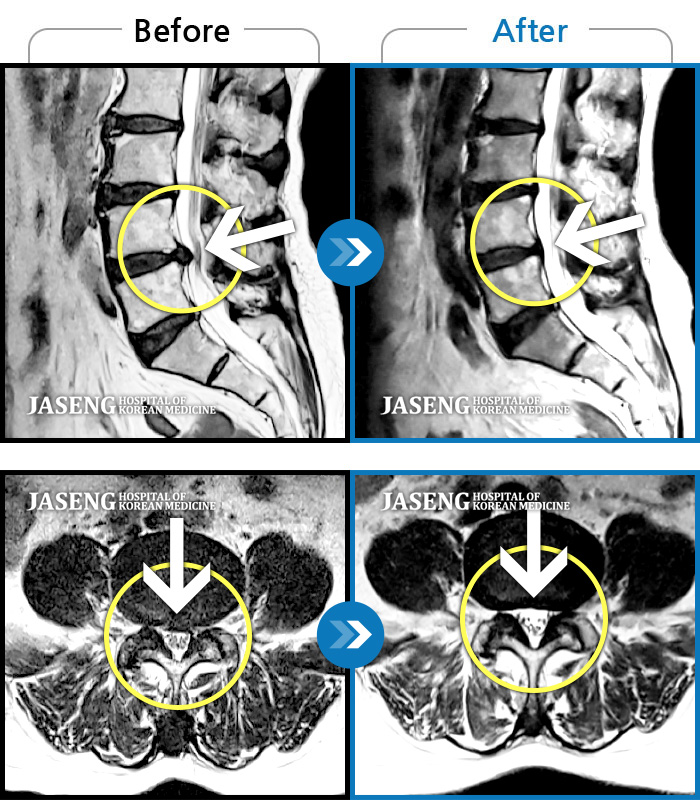

MRI ġ

1,237 MRI ũ ʸ Ȯϼ.